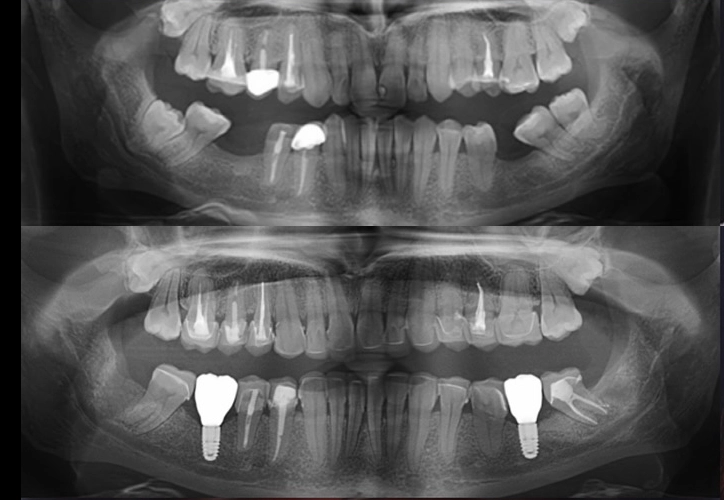

implanturi dentare

Implantologie și estetică dentară: Emanuel Andrițoi